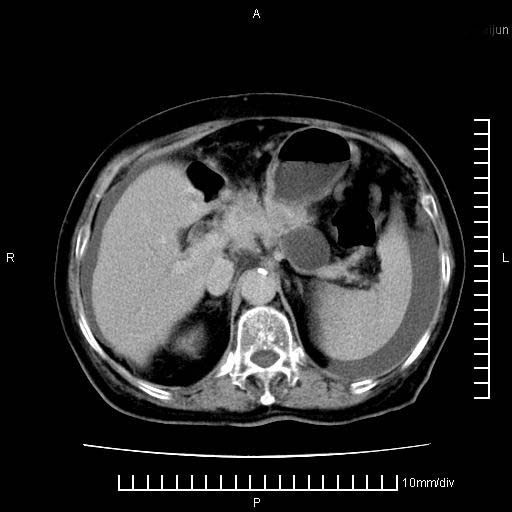

标题: CT28280:腹部增强:女性,80岁

上腹疼痛月余,外院核磁诊断胰腺癌。现临床示右下腹可明显触及包块,可片子上怎么没有看到?

1.胰腺颈体部癌。

2。腹腔积液。

胰腺体部癌累及周围器官,腹膜、粘连

1。胰腺ca伴腹膜腔转移

2。肝左叶低密度灶,考虑转移可能

支持胰腺癌肝内转移,腹水改变。

胰腺结构模糊,胰尾部见囊性包块,周围脂肪密度增高,左肾前筋膜增厚,胸水、腹水。不符合胰腺ca伴腹膜腔转移。考虑胰腺炎伴假性囊肿形成、胸腹腔积液。

1、考虑胰腺癌伴腹膜腔转移,胸腹水。

2、肝脏转移可能。

1)考虑胰腺癌并胰腺假性囊肿形成。2)肝内低密度灶,不排除转移。3)右肾盂积水。4)腹水。5)右侧胸腔积液并右肺下叶部分膨胀不全。